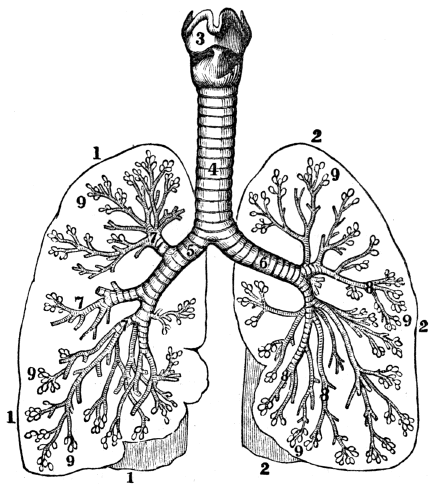

| 23. | Anatomy of the Respiratory Organs, | 209 |

| 24. | Physiology of the Respiratory Organs, | 217 |

| 25. | Hygiene of the Respiratory Organs, | 228 |